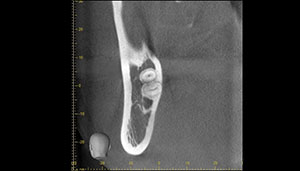

CT

CTで親知らずと神経(下歯槽管)の位置を確認しました。

親知らずと神経は一定の距離があり、麻痺などのリスクがほとんどないと判断できます。